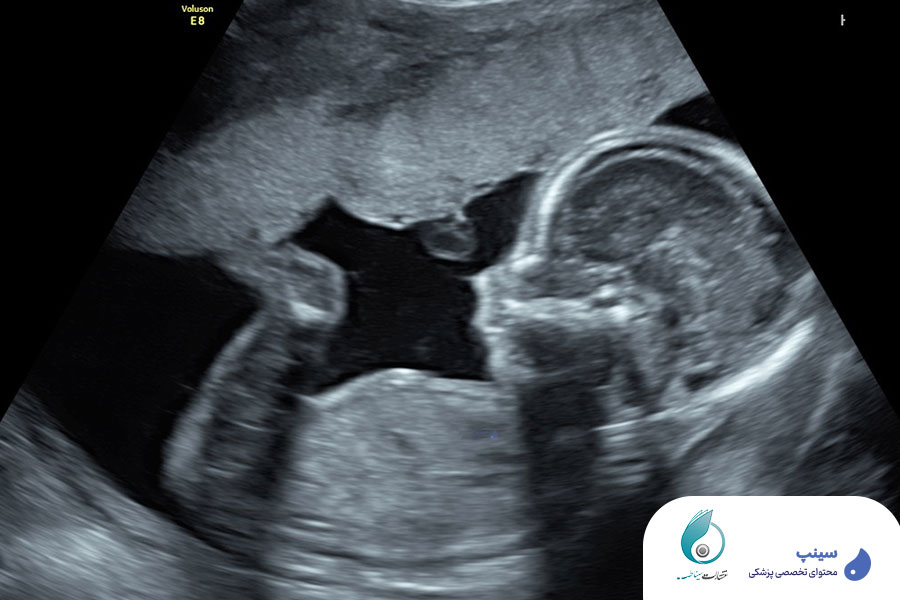

تشخیص زودهنگام ناهنجاریهای جنینی یکی از مهمترین وظایف متخصصان رادیولوژی و سونوگرافی در دوران بارداری است. بررسی دقیق ساختارهای مختلف بدن جنین در مراحل اولیه رشد میتواند به شناسایی مشکلات ژنتیکی و کروموزومی کمک کند و مسیر تصمیمگیری والدین و پزشکان را روشنتر سازد. آنومالی اسکن و آمنیوسنتز جنین از جمله روشهای کلیدی در غربالگری ناهنجاریهای مادرزادی هستند که نیاز به دانش و مهارت بالایی دارند.

در این دوره آنومالی اسکن و آمنیوسنتز جنین بهصورت گامبهگام و کاملاً حرفهای تدریس میشوند. با شرکت در این دوره، شما نهتنها با اصول پایهای این روشهای تشخیصی آشنا میشوید، بلکه یاد میگیرید چگونه این تکنیکها را در شرایط بالینی واقعی به کار بگیرید. در ادامه، جزئیات دقیق هر سرفصل آموزشی این دوره را بررسی میکنیم:

بهترین زمان برای انجام آنومالی اسکن جنین بین هفته ۱۸ تا ۲۲ بارداری است. در این بازه، پزشک میتواند بسیاری از ناهنجاریهای جنینی را با دقت بالا تشخیص دهد.